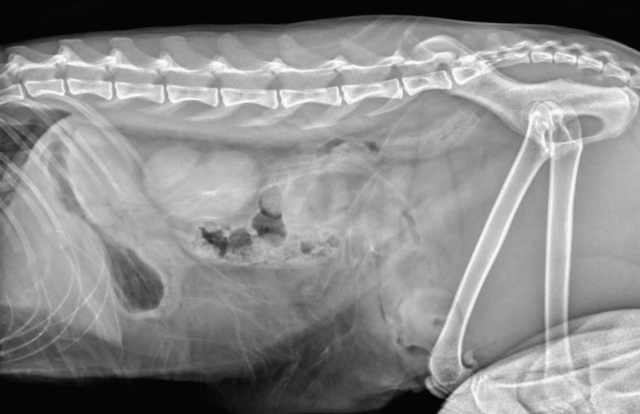

Pelvic trauma is a common finding in feline blunt-trauma patients and survey radiographs are recommended, even in ambulatory cats (Figure 9). Crepitus on manipulation of the pelvic limbs or palpation of fractures directly via rectal examination can provide an initial indication. Sacroiliac, coxofemoral and distal joint luxations, as well as long bone fractures are also fairly common and may be evident on physical examination or can be assessed on survey radiographs. The abdomen should also be carefully palpated for subtler abdominal wall ruptures (Figure 10).